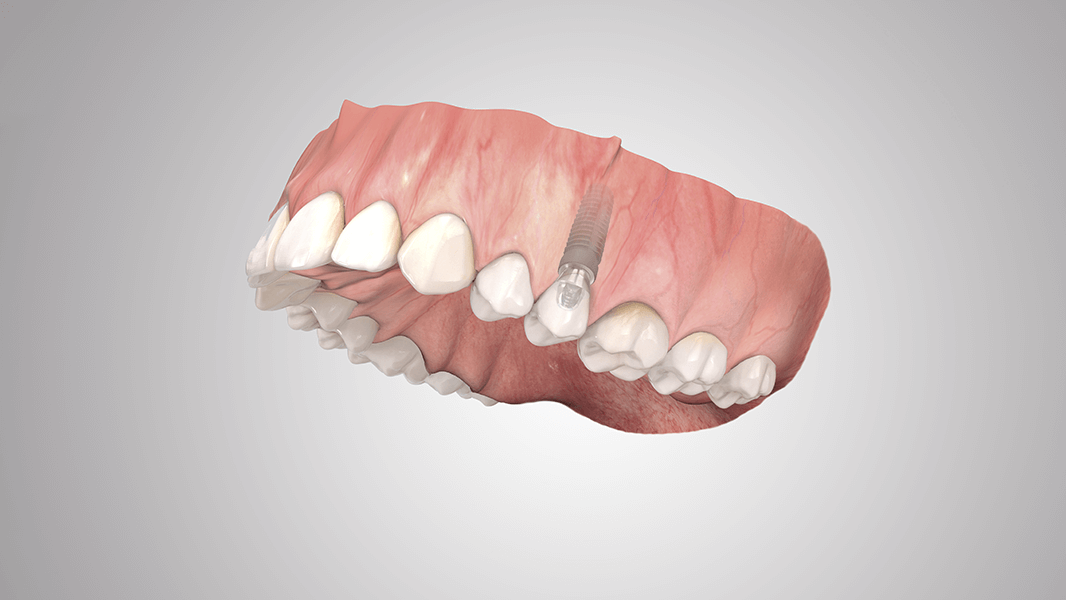

Le système COMFOUR®

Le système de pilier pour restaurations occlusales vissées

Les restaurations vissées occlusales intègrent des structures de pointe. Le système COMFOUR® permet à vos patients édentés d’accéder immédiatement à une restauration confortable et fixe avec quatre ou six implants en général – et par conséquent de gagner nettement en qualité de vie. Pour le praticien, ce nouveau système est également synonyme d’un confort accru et d’une meilleure marge de manœuvre. COMFOUR permet d’envisager plusieurs concepts de traitement. Outre les couronnes et bridges à vissage occlusal utilisés dans le cadre d’une mise en charge immédiate ou différée, ce système à options multiples permet aussi la restauration avec structure sur pilier barre droit et angulé. COMFOUR vous offre une multitude d’options et vous aide à relever les défis du quotidien plus rapidement.

Outre sa diversité, le système prothétique COMFOUR® séduit aussi par son design compact et élégant. Des lignes épurées caractérisent tous les composants, ce qui simplifie nettement la restauration prothétique pour les dentistes et prothésistes. Par ailleurs, avec ses nombreuses innovations techniques, COMFOUR n’est pas seulement un nom, c’est aussi un programme pour utilisateurs et patients. La base de chaque restauration COMFOUR réside dans le pilier barre droit ou angulé. Les piliers barre dont le code couleur correspond au diamètre de l’implant sont disponibles en version droite, angulée à 17° et 30° et dans différentes hauteurs gingivales.